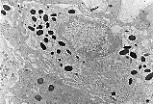

透射电镜(M.E.T.)下可清晰观察到角质形成细胞的基底突起。

角质形成细胞的侧面与相邻细胞紧密嵌合,这种结构增强了表皮的黏附性。 |

透射电镜下,比佐泽罗小体对应于富含桥粒和张力丝的区域。 | |

透射电镜下可见黑素细胞质内的黑素小体,这是高尔基复合体来源的结构, 黑色素的合成在此分多个阶段进行。 | |

透射电镜显示梅克尔细胞质内含有大量 神经内分泌颗粒 。 | |

透射电镜下, 朗格汉斯细胞可通过凹陷的细胞核、淡染且无张力丝和黑素小体的细胞质识别。

其细胞膜与邻近角质形成细胞之间无细胞连接(桥粒)。 |

透射电镜下识别朗格汉斯细胞的最佳方法是:在细胞质内找到特征性的球拍状小体——伯贝克颗粒。 | |